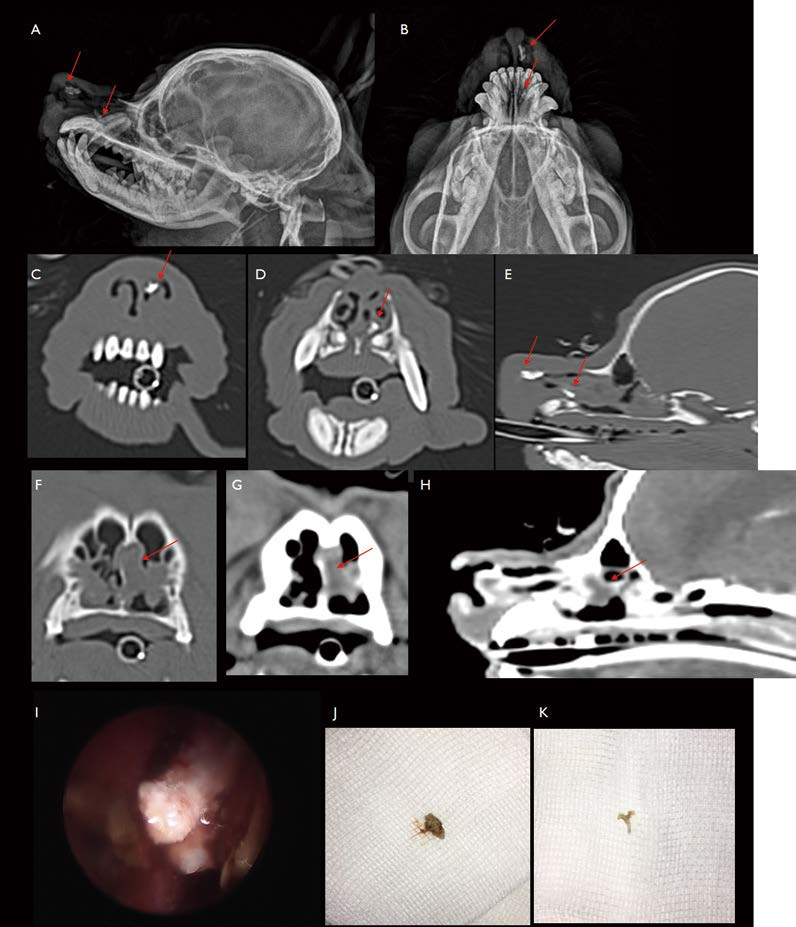

3살 중성화 수컷 Maltese가 20일 동안 sneezing, 코 자극 시 폭발적인 기침 증상으로 내원하였습니다. 내과적 치료에 일시적인 반응 보였으나, 최근 좌측 비강에서 농성 분비물 증가하고 증상이 악화되어 내원하였습니다. Plain X-ray에서는 유의적 이상 소견이 관찰되지 않아, CT 촬영을 하였습니다. CT 검사에서 좌측 nostril부터 dorsal nasal meatus의 rostral part에서 고감쇠의 rim으로 둘러싸인 작은 tubular-like appearance 구조물(그림 1. A, B, C)이 관찰됩니다. 주변으로 삼출물 축적 및 점막 부종 소견 관찰되어 foreign body rhinitis로 진단할 수 있었습니다. Anterior rhinoscopy로 풀씨 이물과 이로 인한 점막 염증 소견(그림 1. D, E, F) 관찰할 수 있었으며, 이물 제거 후 환자는 잘 회복하였습니다.

CT에서 좌측 nostril 후방 dorsal nasal meatus 및 canine tooth level의 ventral nasal meatus 위치에서 방사선불투과성의 이물 또는 rhinoliths가 관찰됩니다(그림 3 C, D, E). 또한 좌측 common nasal meatus에서 tubular-like appearance 음영이 관찰됩니다(그림 3 F, G, H). Rhinoscopy를 통해 rhinoliths 관찰, 직접 제거하고, common nasal meatus 위치의 연조직 밀도의 이물은 강한 nasal flushing으로 제거하였습니다(그림 3. I, J, K).